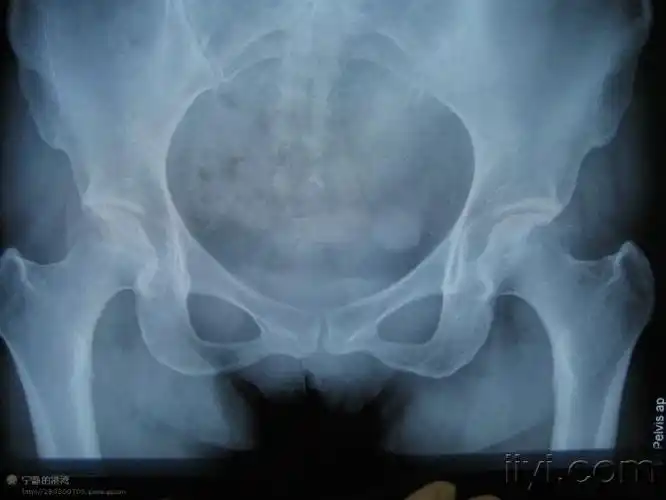

股骨头坏死x线图

照片中可以看到股骨头明显塌陷,软骨打皱.